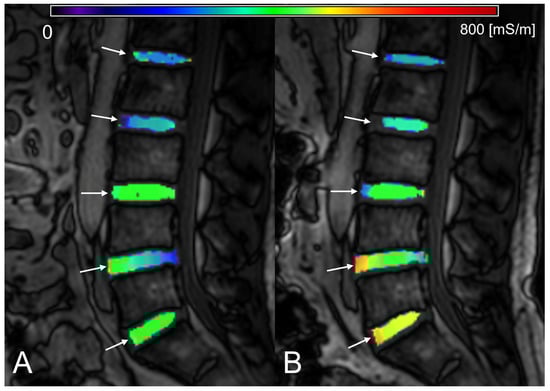

| σ [mS/m] | Morning | 374.696 ±123.957 | 333.879 ±155.562 | 365.987 ±93.528 | 440.309 ±98.890 | 375.274 ±96.922 | 361.091 ±149.300 |

| (94.83 − 770.99) | (137.39 − 770.99) | (209.03 − 568.22) | (295.05 − 605.21) | (186.04 − 520.26) | (94.83 − 717.46) | ||

| Evening | 401.607 ±113.978 | 348.211 ±81.711 | 396.742 ±108.578 | 420.614 ±99.149 | 440.663 ±98.776 | 403.005 ±160.339 | |

| (108.88 − 777.75) | (241.14 − 492.45) | (177.25 − 556.25) | (182.58 − 609.89) | (299.25 − 585.64) | (147.30 − 661.28) | ||

| N | 83 | 17 | 17 | 16 | 17 | 16 | |

| p | 0.035 | 0.554 | 0.236 | 0.492 | 0.010 | 0.134 | |